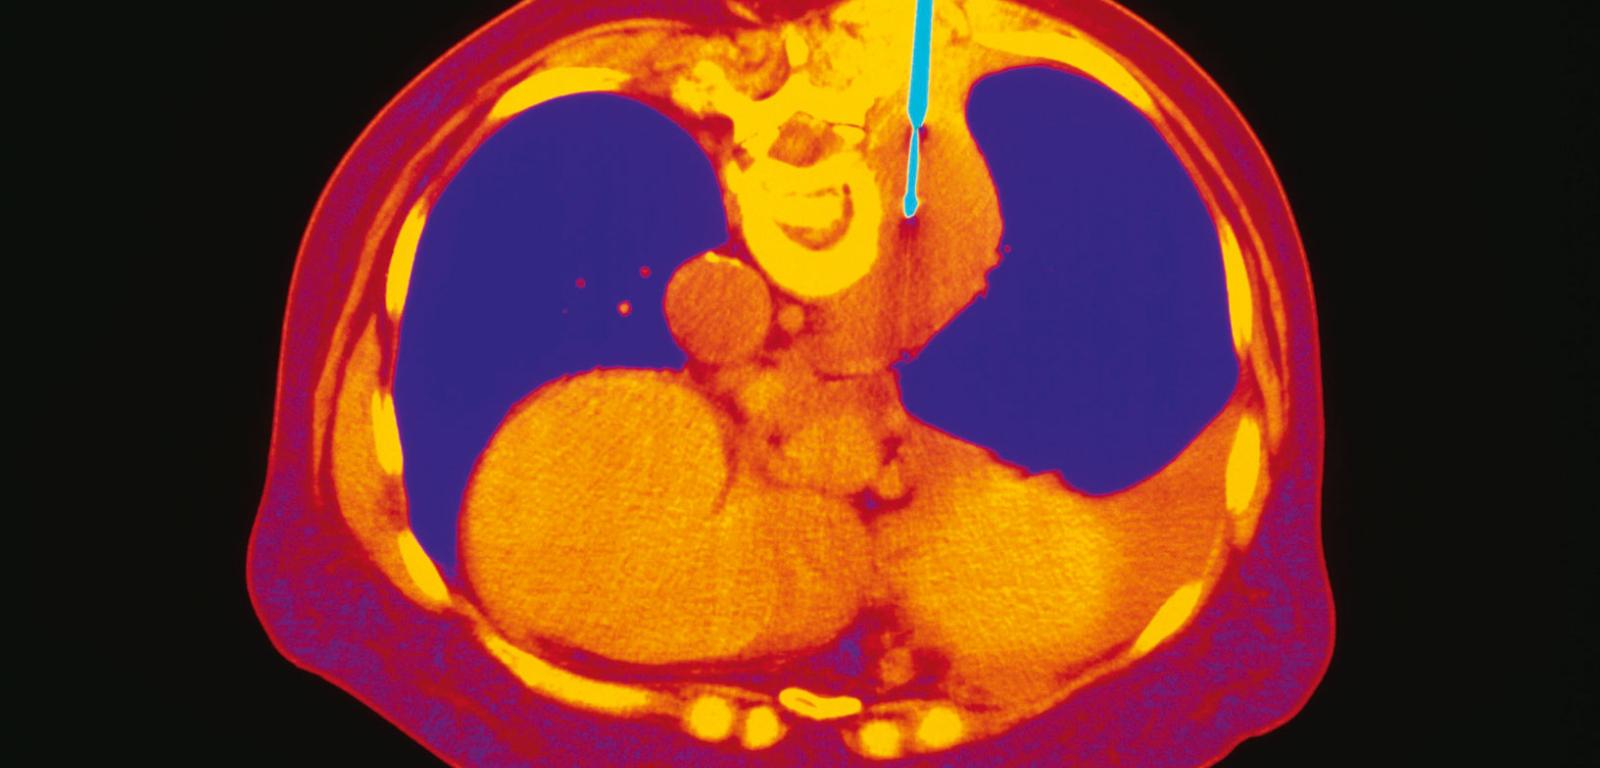

Biopsja aspiracyjna płuc – koloryzowane zdjęcie TK. Bronchoskop (niebieski) z wysuwalną igłą pobiera tkankę. Widoczne m.in. płuca (fioletowy), kręgosłup (żółty, obok bronchoskopu), badany guz (ciemnopomarańczowy). Na dole strona brzuszna. Biopsja aspiracyjna płuc – koloryzowane zdjęcie TK. Bronchoskop (niebieski) z wysuwalną igłą pobiera tkankę. Widoczne m.in. płuca (fioletowy), kręgosłup (żółty, obok bronchoskopu), badany guz (ciemnopomarańczowy). Na dole strona brzuszna. Indigo